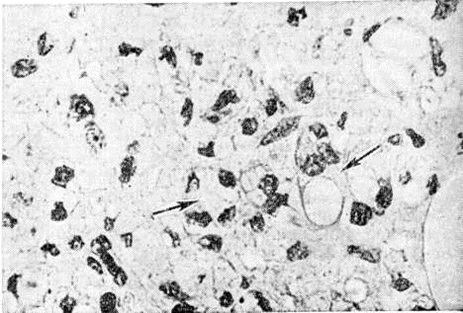

Электронно-микроскопическими исследованиями установлено, что ультраструктура возбудителя Лепра принципиально не отличается от строения других видов грамположительных бактерий. На поверхности микобактерий Лепра выявляется равномерный электроннопроницаемый (осмиофобный) слой толщиной 5—10 нанометров (наружный диффузный слой клеточной стенки). За ним следует осмиофильный слой клеточной стенки толщиной от 3 до 10 нанометров, состоящий из двух очень тонких некоторое, плотно прилегающих друг к другу. Непосредственно к внутренней поверхности клеточной стенки примыкает наружный слой цитоплазматической мембраны (рисунок 1), представляющей собой, как и у других бактерий, трёхслойную мембрану толщиной 7,5—9 нанометров. В бактериальной клетке встречаются 1—2 мезосомы с выраженным полиморфизмом (петлеобразные, везикулярные, трубчатые, пластинчатые, гроздевидные). В цитоплазме выявляется сравнительно небольшое количество рибосом, сферические электронно-плотные включения волютина диаметром 20—50 нанометров, включения, имеющие вид ограниченных мембраной вакуолей (предположительно липоиды), и гомогенные тельца, природа которых остаётся неизвестной. Ядро не имеет определённой формы, расположено в центре клетки вдоль её длинной оси, не ограничено мембраной. Иногда в лизирующихся под воздействием химиотерапии клетках микобактерий Лепра выявляются спороподобные образования (рисунок 2 и 3).

Основным способом размножения микобактерий Лепра является деление материнской клетки и врастания поперечной перегородки. Микобактерия Лепра является облигатным внутриклеточным паразитом тканевых макрофагов или клеток ретикулоэндотелиальной системы, проявляет выраженный тропизм к коже и периферическим нервам, но на поздних стадиях развития процесса встречается также во многих других клетках и тканях организма. В тканевой клетке микобактерии Лепра размножаются только в цитоплазме (рисунок 4); внутриядерный паразитизм для них нехарактерен. Микобактерии в лепрозных клетках иногда отграничены от цитоплазмы клетки-хозяина фагосомной мембраной. На поздних стадиях инфекции паразитирование возбудителей Лепра человека сопровождается нарушением строения эндоплазматического ретикулума и митохондрий клетки-хозяина.